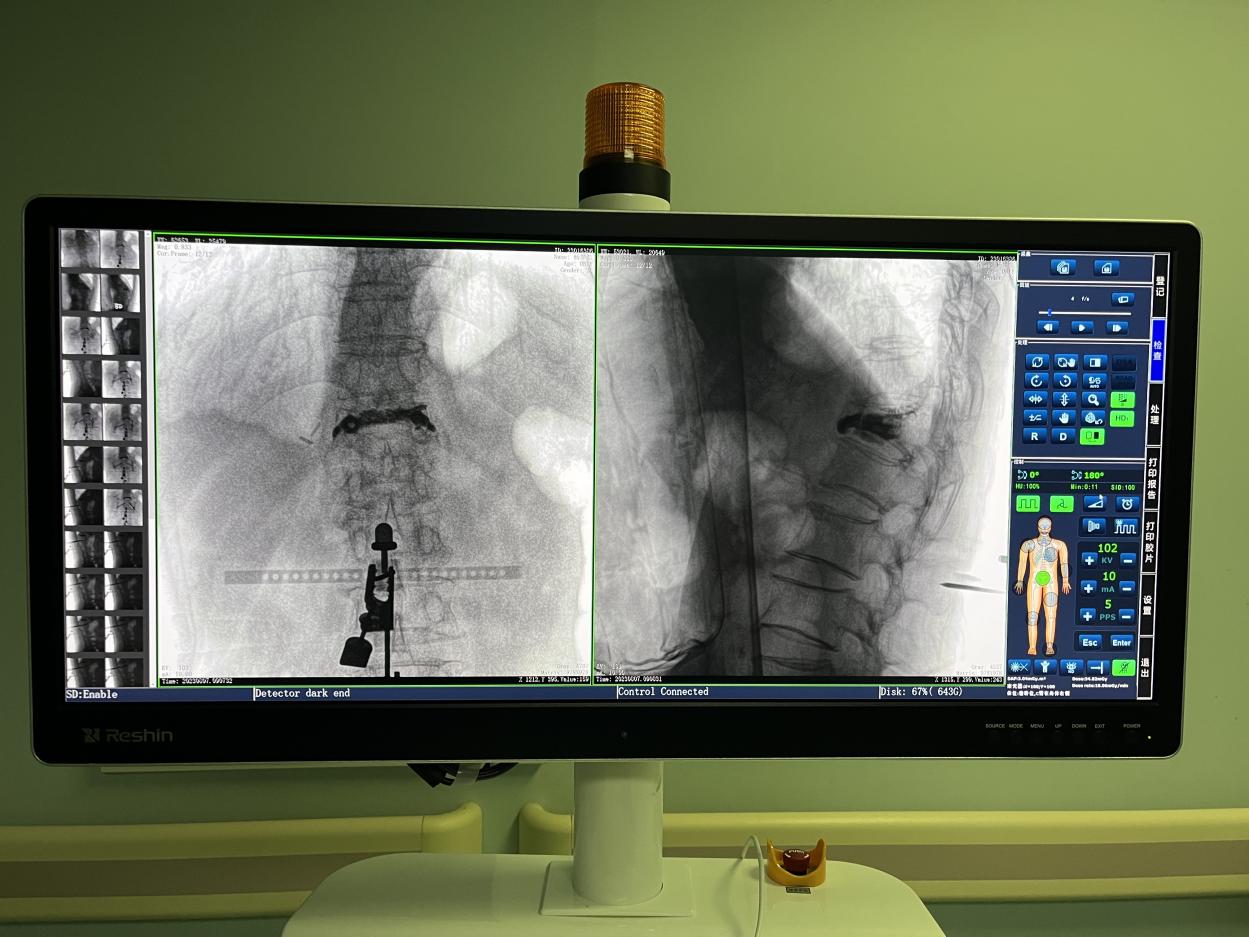

1.三維術(shù)中圖像

PL300B搭配普愛醫(yī)療自主研發(fā)生產(chǎn)的平板三維C形臂使用,通過三維立體術(shù)中圖像,手術(shù)醫(yī)生可從各個(gè)方位觀察合適的手術(shù)入路,并進(jìn)行關(guān)鍵數(shù)據(jù)測量,從而最大限度地避開危險(xiǎn)區(qū)。

骨科機(jī)器人手術(shù)-術(shù)中影像